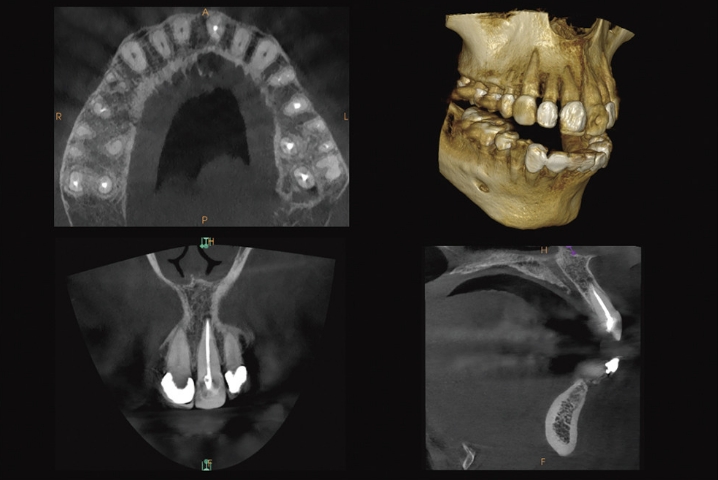

難治症例に対しては、低線量歯科用CTレントゲンを用いて原因の追及をする事も可能です。

レントゲンでは発見困難な病巣の広がりや根管形態を3Dで確認できます。